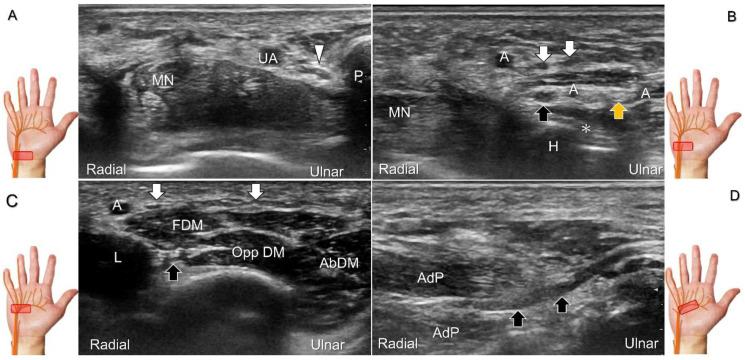

手腕/手部远端周围神经病变的超声成像与引导

超声已成为一种极具价值的工具,用于腕部区域周围神经病变的成像,特别是对于诸如腕管综合征和尺神经管综合征等常见病症。大量研究表明,神经在卡压部位近端肿胀、边界不清和平扁是神经卡压的特征。然而,关于腕部和手部的小神经或终末神经的信息却很匮乏。本文旨在通过全面概述这些神经卡压的扫描技术、病理学和引导注射方法来填补这一知识空白。本综述详细阐述了正中神经(主干、掌皮支和返支)、尺神经(主干、浅支、深支、掌尺皮支和背尺皮支)、桡浅神经、骨间后神经、掌总/指固有神经和背总/指固有神经。一系列超声图像用于详细说明这些技术。最后,超声检查结果补充了电诊断研究,有助于更好地理解整个临床情况,而超声引导下的干预措施对于治疗相关神经病变是安全有效的。